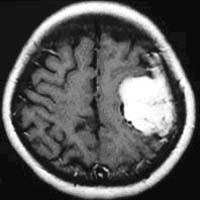

脳動静脈奇形に対する液体塞栓物質を用いた治療

治療により異常血管は閉塞されました。